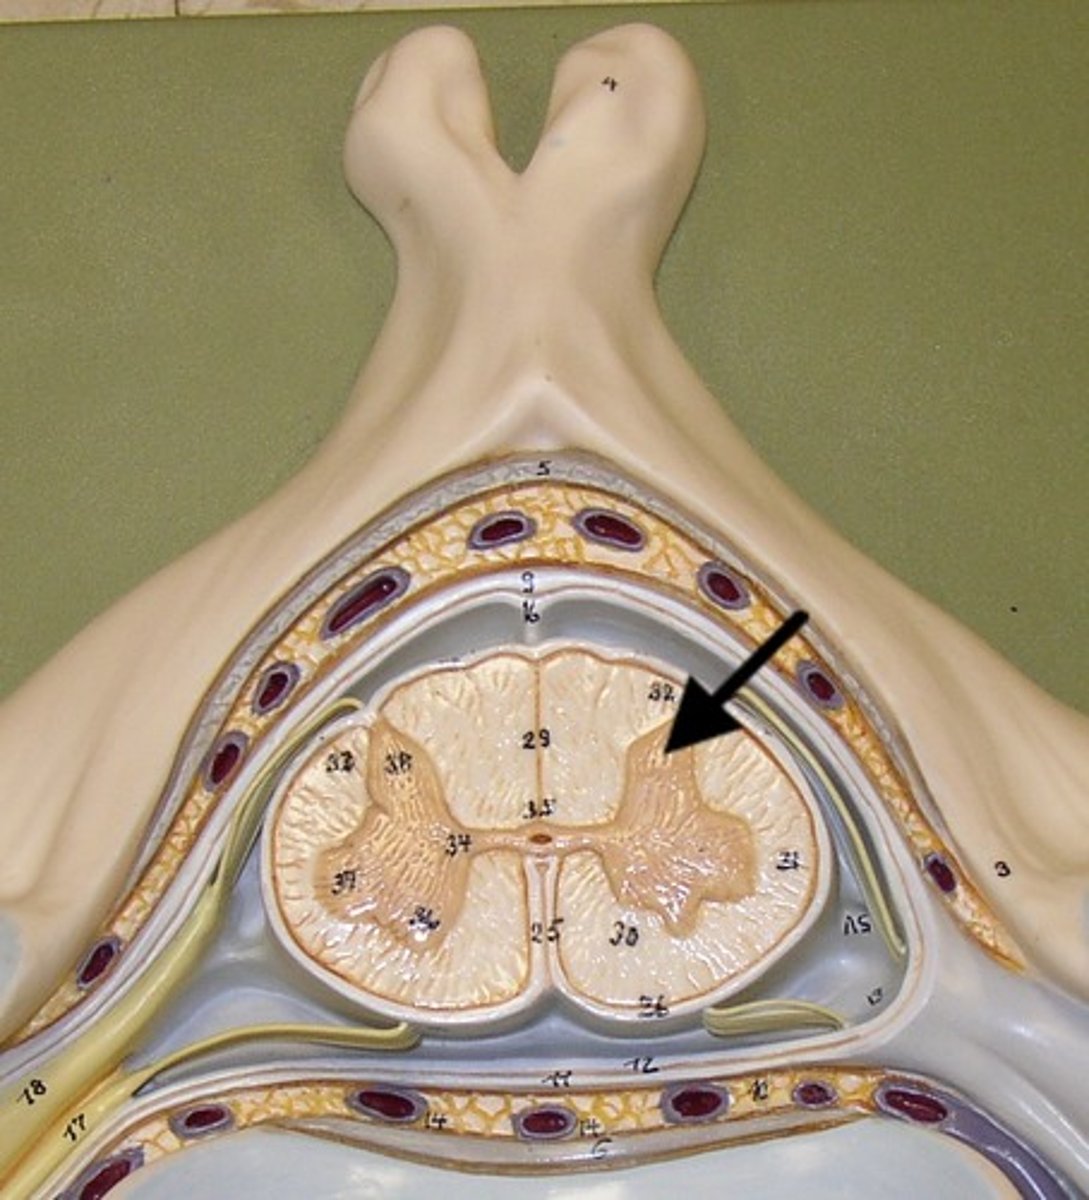

Spinal cord Anatomy (cross-sectional)

1)Internal butterfly shaped gray matter,

2)Exterior white matter,

3)Central canal filled with cerebrospinal fluid (CSF),

4)Cushioned & protected by meninges,

5)Pia mater,

6)Spinal nerves leave at the level of each vertenrae

Horns of Spinal Cord Anatomy

Dorsal Horns,

Ventral Horns,

Lateral Horns

Dorsal Horns

Lateral Horns

Ventral Horns

Interneurons

exterior white matter of the spinal cord

Ascending (sensory) and descending (motor) myelinated nerve tracts,

Posterior, anterior, lateral columns or funiculi

Posterior Columns

Anterior Columns

Lateral Columns/ funiculi

Central canal filled with what?

Central canal filled with cerebrospinal fluid (CSF)

Cushioned and protected by meninges

1) Cover the spinal cord

2) Dura mater, Arachnoid & Pia mater

dura mater of spinal cord

1) Separated from the periosteum by the epidermal space (fat, blood vessels)

2) Subdural space between dura and arachnoid mater

Dura Mater